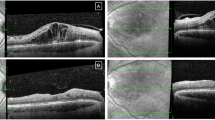

Treatment with intravitreal corticosteroids may be considered in some pregnant women with macular oedema associated with diabetes (diabetic macular oedema, DMO), retinal vein occlusion, or uveitis. Intravitreal corticosteroid agents differ in their characteristics. In particular, intravitreal triamcinolone does not achieve significant systemic serum levels and may therefore be considered safe in pregnancy [4]. Systemic dexamethasone doses from an intravitreal slow-release implant (Ozurdex®) are not thought to be high enough to be clinically relevant. Several case reports describe intravitreal triamcinolone and dexamethasone for the treatment of DMO in pregnant women with favourable outcomes both for the retina and the pregnancy [13, 16, 17]. Although a population-based cohort study from France suggested a high incidence of obstetric complications in pregnant women treated with intravitreal corticosteroids, this was thought to be related to maternal age and the underlying systemic comorbidities (e.g. diabetes, hypertension) driving the need for treatment in the first place [18].

Intravitreal anti-VEGF agents such as aflibercept (Eylea®), ranibizumab (Lucentis®), bevacizumab (Avastin®) and increasingly faricimab (Vabysmo®) are commonly used in non-pregnant patients for the management of several chorioretinal diseases such as macular neovascularisation (MNV) (related to age-related macular degeneration (AMD), myopia, inflammatory chorioretinal diseases or other secondary causes), DMO, cystoid macular oedema related to retinal vein occlusion, and radiation maculopathy. However, some ophthalmologists may be hesitant to prescribe them to pregnant women because VEGF is required in modulating placental and embryonic vascular development, meaning that systemic absorption of anti-VEGF could theoretically affect the pregnancy. This has contributed to a paucity of data on maternal and fetal outcomes [70, 71].

A systematic review of cases treated with intravitreal anti-VEGF in the literature identified 41 women who were treated over the course of 42 separate pregnancies [9]. Bevacizumab (n = 22, 54%) and ranibizumab (n = 17, 41%) were administered more frequently than aflibercept (n = 2, 5%), although up to 40% (n = 6) were treated early in the first trimester before their pregnancy was recognised, meaning that pregnancy status was not a consideration for anti-VEGF agent in many cases. In terms of pregnancy outcomes, the majority (n = 34, 81%) resulted in live births, five of which were complicated by pre-eclampsia, premature delivery, and/or IUGR, all in women with significant risk factors for these adverse pregnancy outcomes, such as pre-existing diabetes. There were three stillbirths in women with complex obstetric histories, such as recurrent miscarriages or stillbirths. There were five early-term miscarriages, which comprised four women with additional risk factors for poor pregnancy outcomes, and one very early pregnancy loss at four weeks’ gestation. Miscarriage in early pregnancy is common, so a direct association between obstetric outcomes and anti-VEGF treatment cannot be drawn. Published data on neonatal complications were limited.

Given the limited safety data on the use of anti-VEGF agents in pregnant women, we would recommend a multidisciplinary team approach to include obstetric physicians/obstetricians, ophthalmologists, and any relevant specialist physicians involved in their medical care when deciding on whether to proceed with anti-VEGF treatment. Patients should be appropriately counselled and actively involved in the decision-making process, with opportunities offered to have a detailed discussion of the potential risks, benefits, and alternatives with a knowledgeable clinical team. This may include observation without treatment, or alternatives such as Ozurdex® for conditions such as diabetic macular oedema or cystoid macular oedema associated with retinal vein occlusions. However, Ozurdex® is less suitable for steroid responders, and confers a risk of cataract formation with repeated treatments, although development of a visually significant cataract with a single implant is unusual in uncomplicated injections [76]. For other sight-threatening conditions, such as MNV, where there are no other therapeutic options aside from anti-VEGF agents to preserve vision, multidisciplinary team discussion becomes even more essential.